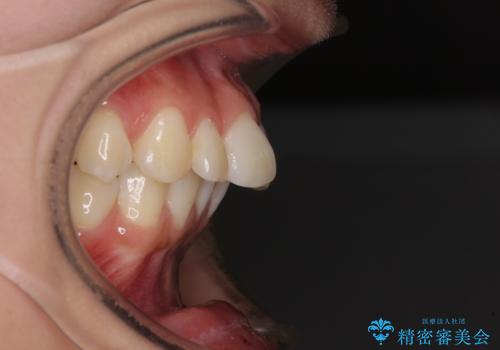

- 口を閉じたときに唇の間から飛び出してくる前歯を気にして来院された患者様です。

骨格的に上顎骨が前方位にあるため、左右の第一小臼歯を抜歯し、ワイヤー装置にて咬み合わせを整えていくこととしました。

前歯の突出感が改善されるだけでなく、奥歯の咬み合わせも改善され、食いしばりをしにくい状態に仕上げることができました。